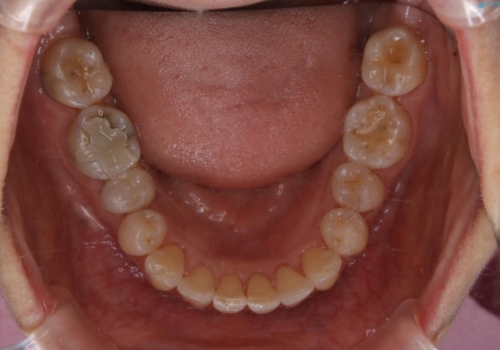

前歯を乗り越える治療はワイヤーの方が有利ではありますが、インビザライン単独でも行うことができます。

患者様によっては乗り越えるタイミングだけワイヤーを装着し、そのあとでまたインビザラインに戻るという方もいらっしゃいます。